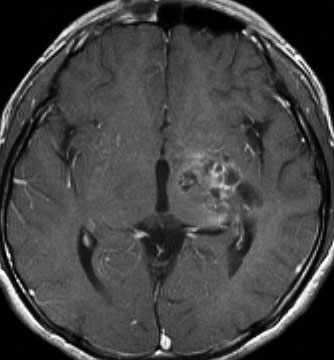

14歳で右の片麻痺と学力の低下で発症しました。ガドリニウム造影がまだらで最初は膠芽腫かな?と思いましたが,mass effectが軽いことが解ります。geminomaとしては珍しいのですがperifocal edemaがあります。

定位生検術で病理組織診断をして化学療法を加えた後の画像です。germinomaのお約束どおり,化学療法できれいに消失します。ちょっとした小さな増強される部分が残るのですがこれはstromal reaction (gliofibrosis)をみているので,残存腫瘍ではありません。余分な追加の放射線治療をしないように気をつけます。